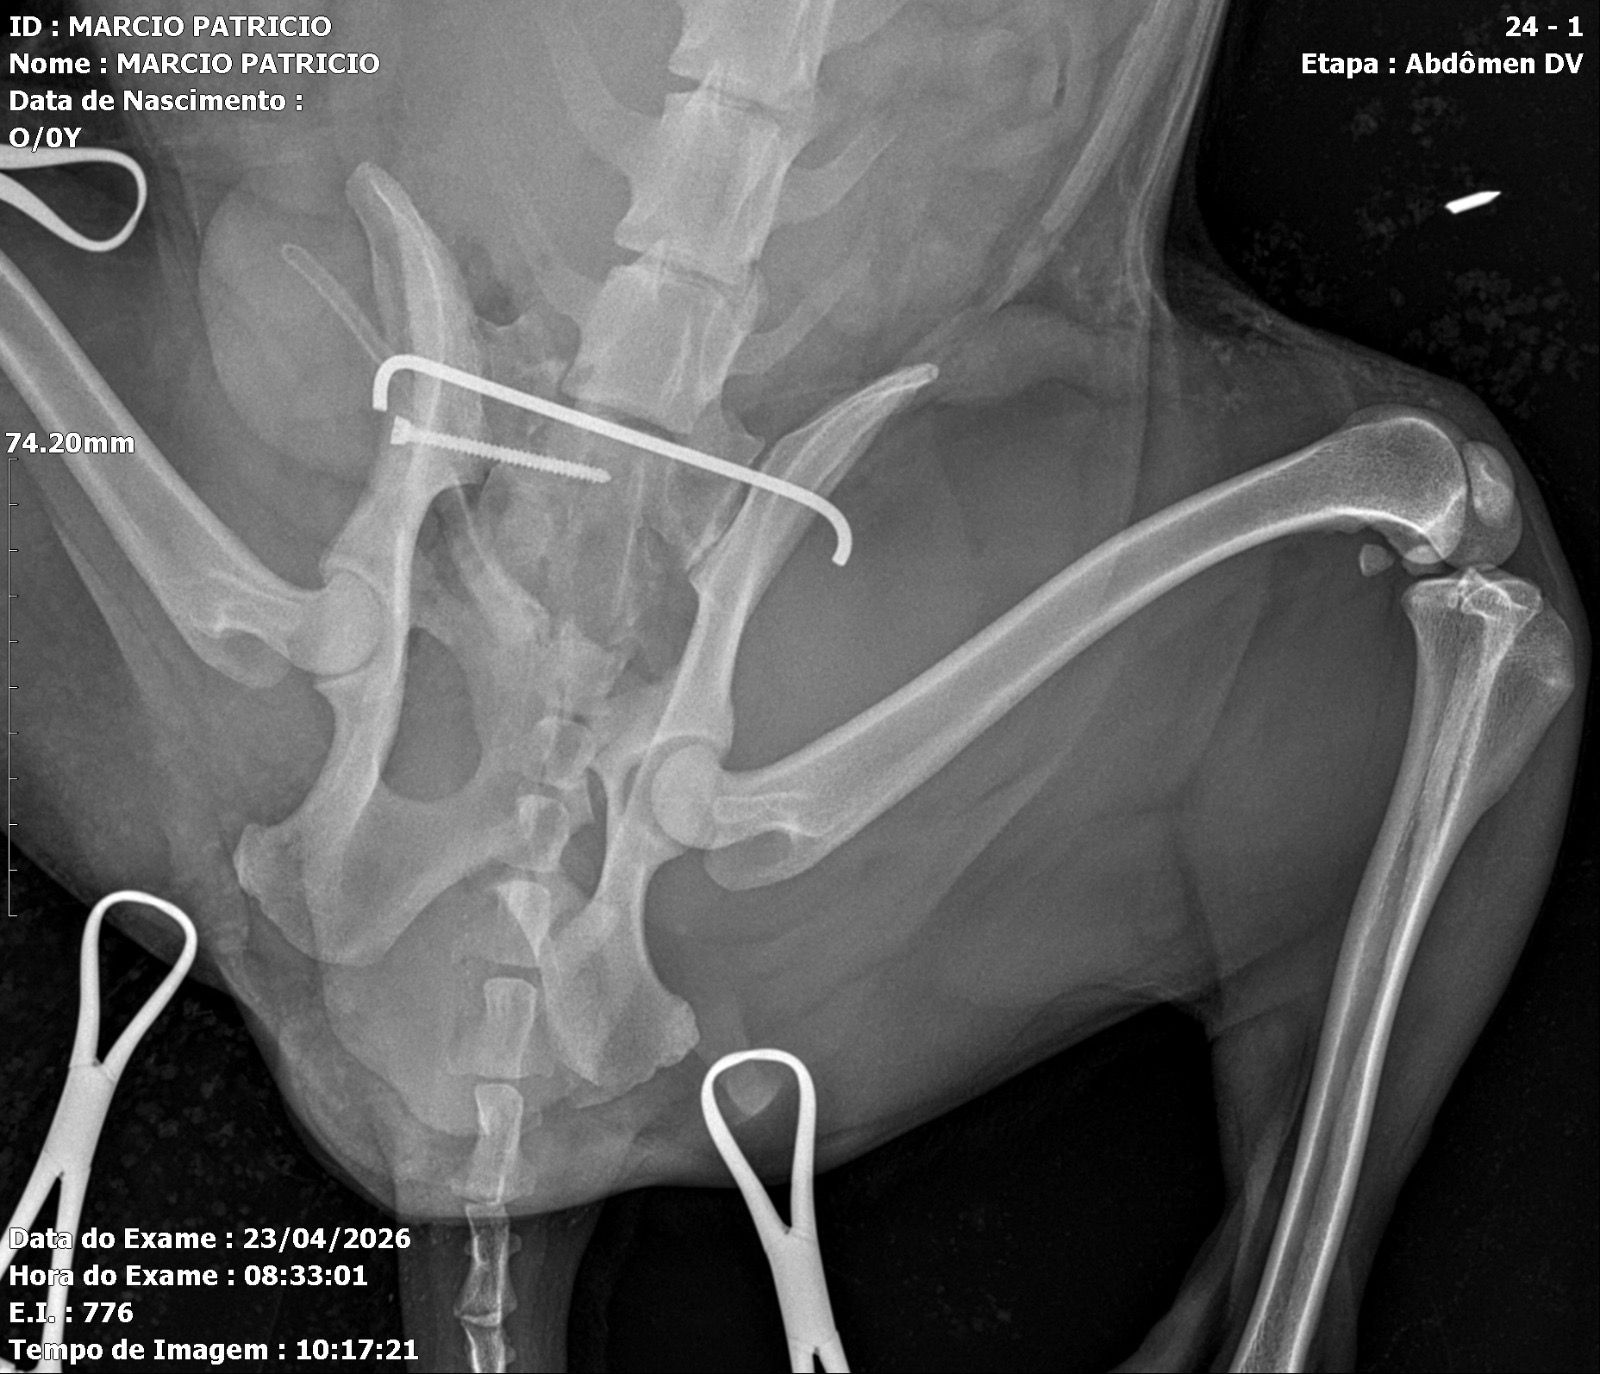

Ele foi atropelado por um carro no dia 21/04/26 e precisou passar por cirurgia de emergência para reconstrução da região da bacia, com colocação de prótese metálica.

Graças à mobilização de amigos, moradores e esportistas da comunidade, conseguimos prestar os primeiros socorros e garantir o atendimento veterinário imediato. A cirurgia foi um sucesso, mas os custos com internação, exames, medicamentos e fisioterapia continuam.